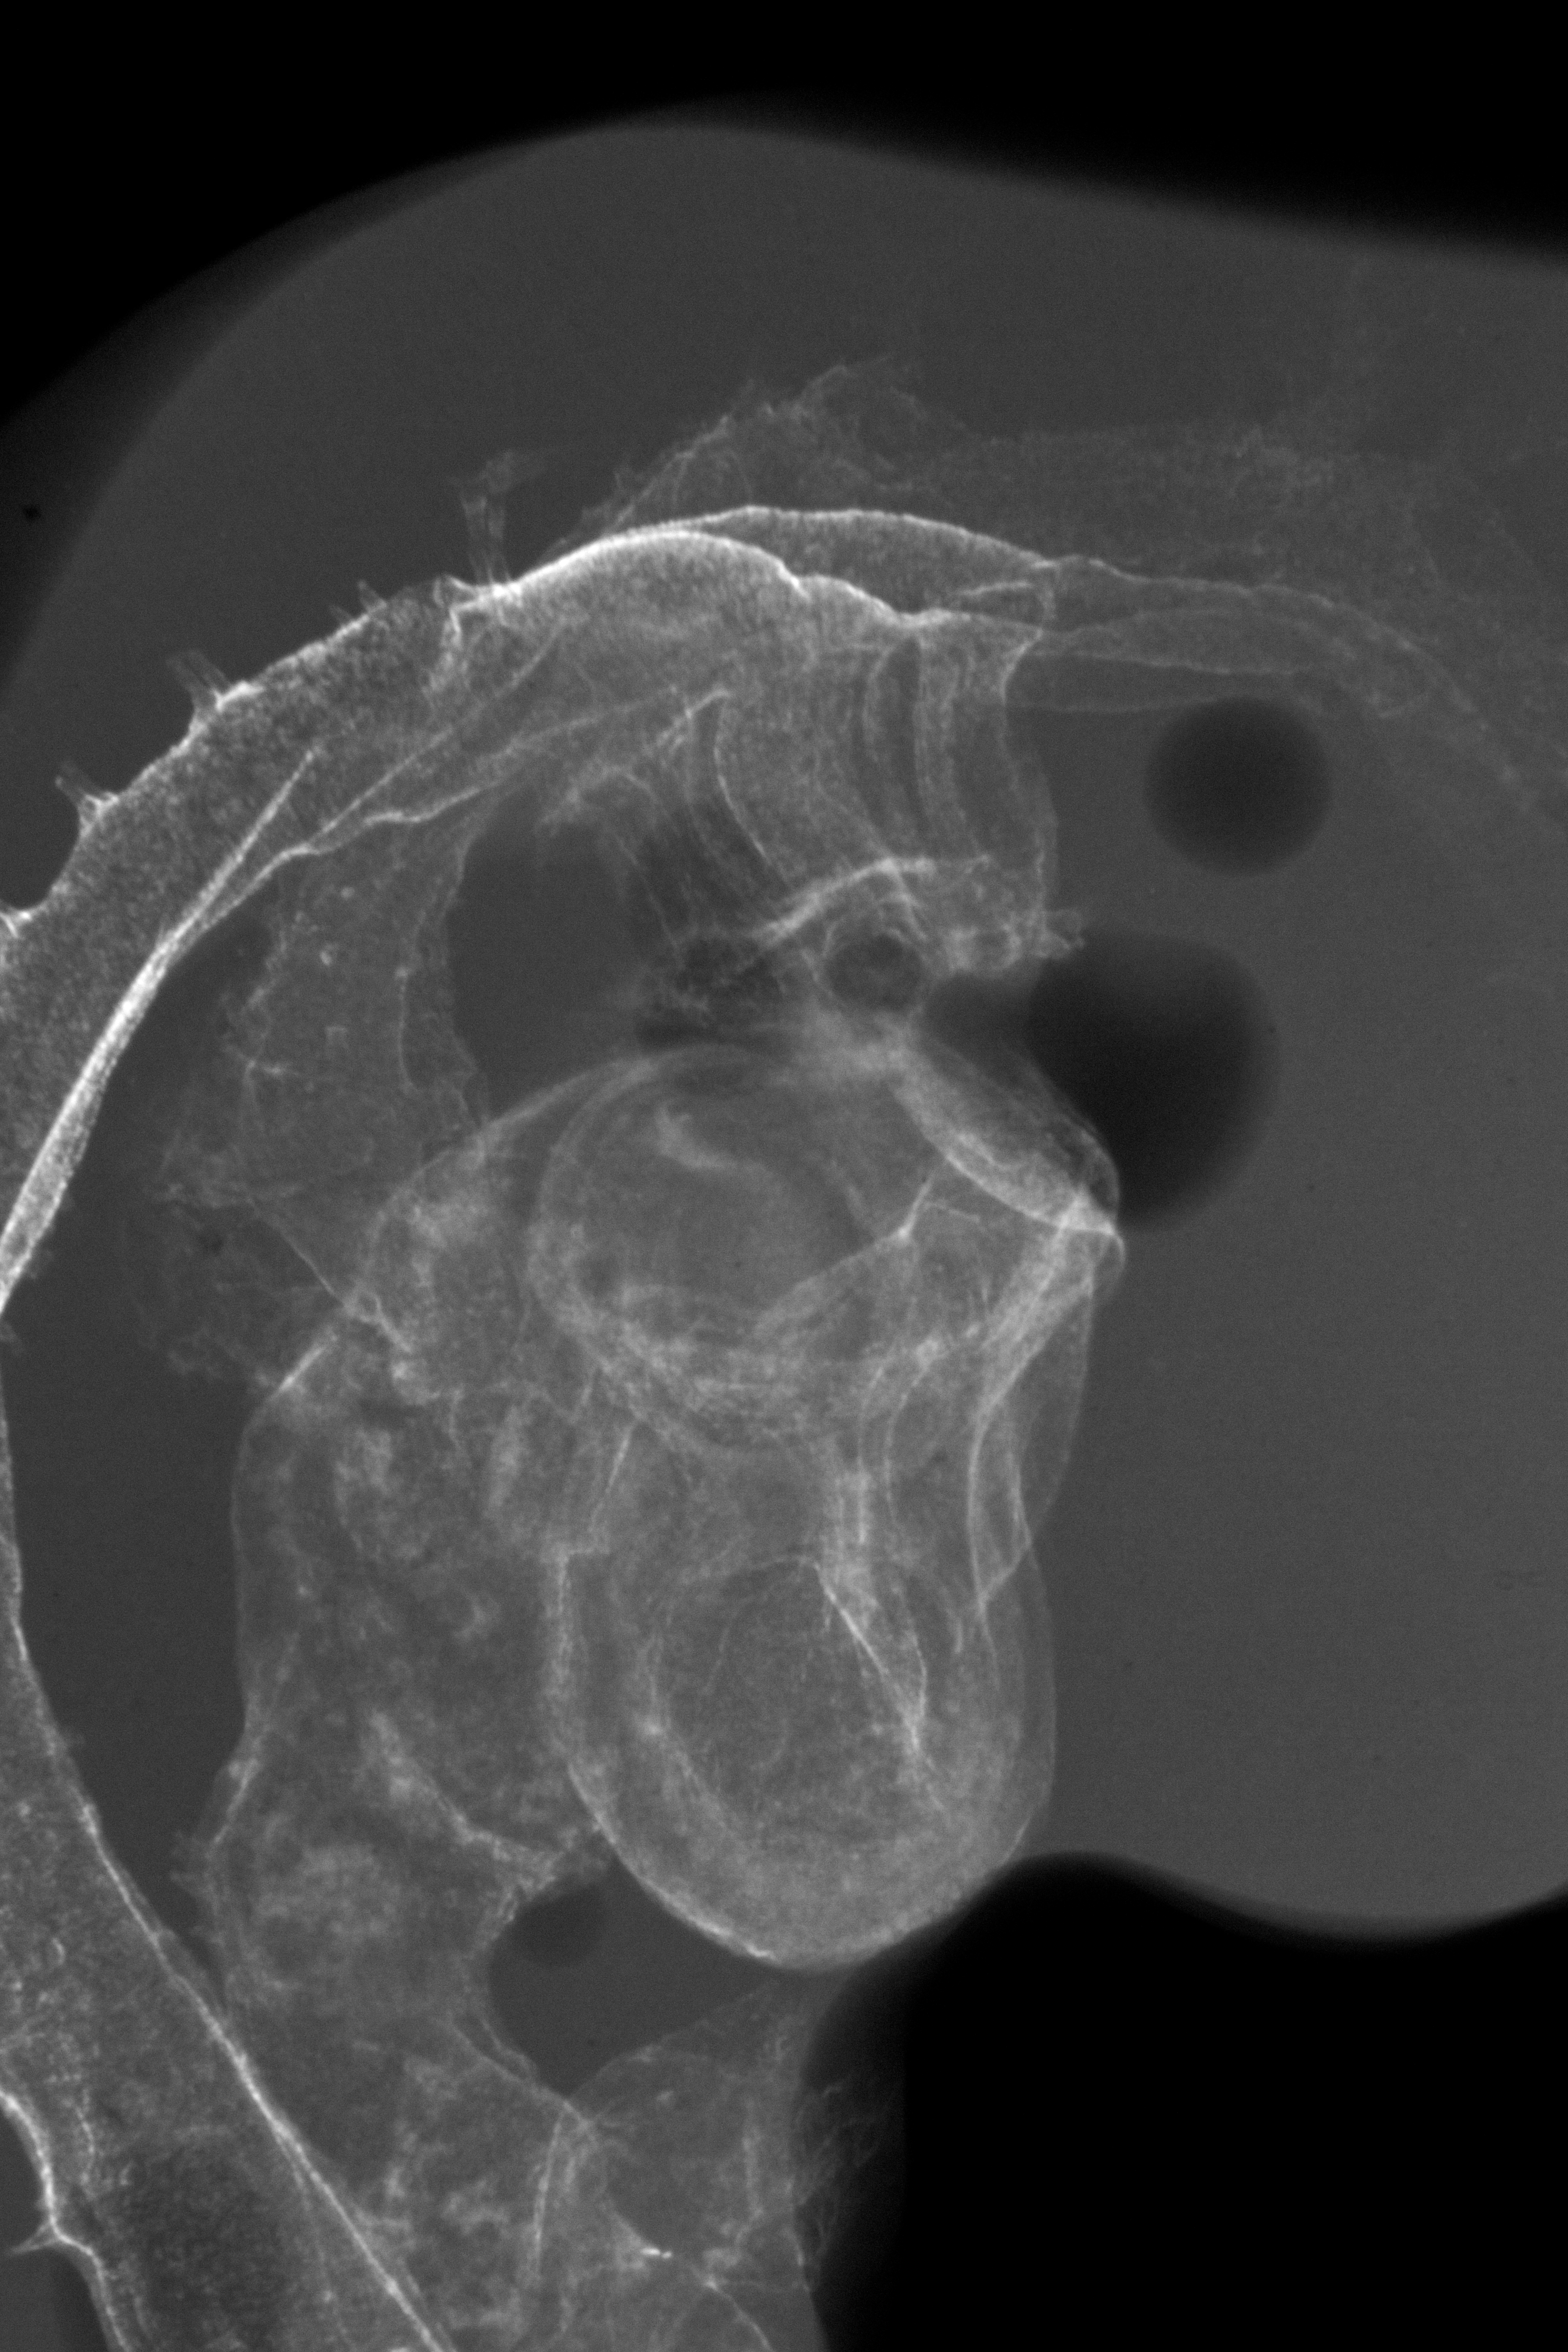

Chick Embryo Microangiography

Hamburger-Hamilton (HH) Stage 20 (approx. 3 - 3.5 days)

X-Ray Micrographs